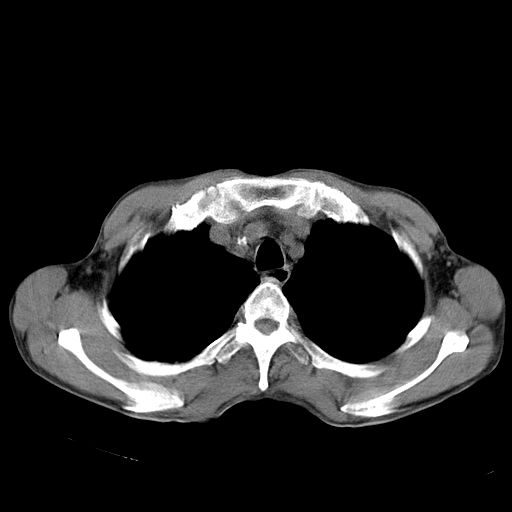

以下是引用苯小孩在2007-5-24 12:47:00的发言:[br]右侧肺门处不均匀密度软组织块影,远端肺组织见斑片模糊影,纵隔内淋巴结明显肿大,边界不清.<纵隔窗第12层面支气管内似见软组织结节>[br]考虑:1、右侧中央性肺癌并阻塞性肺炎并纵隔淋巴结转移可能性大.建议强化或纤支镜进一步检查.[br]2、隆突下淋巴结肿大/食道病变?请做鉴别检查.

以下是引用zhangzhongshou在2007-5-24 12:55:00的发言:[br]1、右肺中叶中心型肺癌并右肺门、隆突下、纵隔淋巴结转移。右肺中叶阻塞性肺炎。

以下是引用jw-830在2007-5-24 15:24:00的发言:[br][br] [br] 考虑右肺中央型肺癌并阻塞性炎症,右肺门及纵隔淋巴结转移。 [br] [br][br]